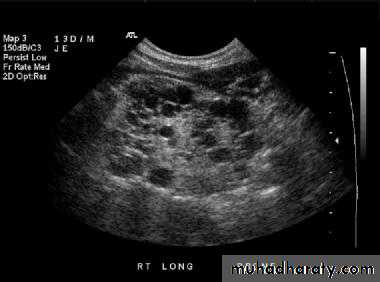

Polycystic renal disease in ultrasound demonstrate numerous cysts seen in cortex & medulla